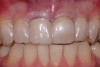

Fig 8. Case 1: A patient presented in January 2006 with a large periapical lesion, a root fracture, and significant buccal bone loss.

Figure 8

Fig 9. Despite the extent of bone loss revealed radiographically, multiple surgical grafting procedures were not indicated. Instead, a flapless surgery would be performed and biologic innovations used to facilitate ridge preservation.

Figure 9

A patient presented with a large periapical lesion, root fracture, and significant loss of buccal bone (Figure 8 and Figure 9). Treatment for this case involved an autogenous bone graft, then implant placement and connective tissue grafting. Recombinant human platelet-derived growth factor-BB was used for ridge preservation and minimally invasive esthetic implant site development with a flapless approach.